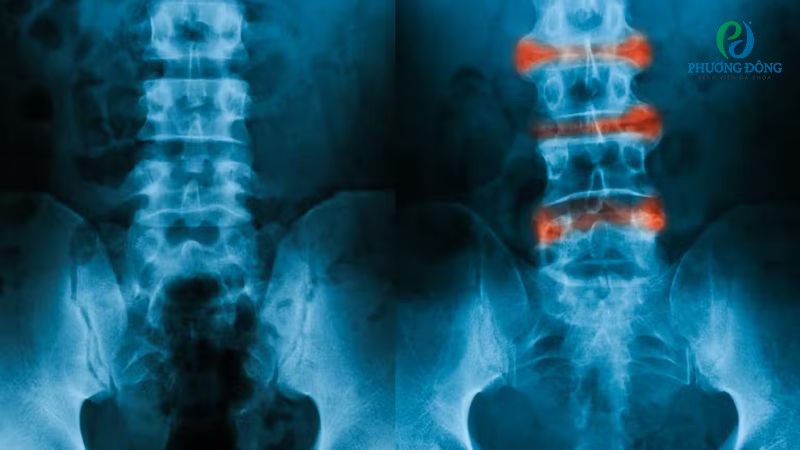

Viêm cột sống dính khớp là một bệnh lý mạn tính, thường gây triệu chứng suốt đời. Tuy nhiên nếu được can thiệp sớm, đúng phác đồ cùng chế độ sinh hoạt hợp lý, người bệnh có thể duy trì tình trạng sức khoẻ ổn định.

Đến nay chưa có phương pháp điều trị dứt điểm viêm cột sống dính khớp, mục tiêu hiện tại chỉ nhằm thuyên giảm triệu chứng và kiểm soát bệnh tiến triển. Tuỳ mức độ tổn thương bác sĩ sẽ chỉ định can thiệp bằng thuốc, tập phục hồi chức năng hoặc phẫu thuật thay khớp.